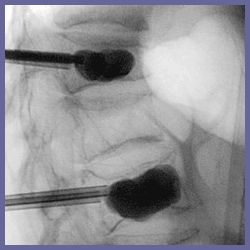

在局部麻醉下,利用可整的X光找到的入,把一枝4mm治扎入椎,注入人工骨泥

2000到2003年主任在庚院院及新竹偕院共治150位脊椎骨折的病患,一共治160脊椎,包括50位男性和100位女性,年平均69. 胸椎100位,腰椎60位,骨症引起椎骨折的有146位,血管瘤1位,移椎瘤3位.多性骨髓瘤1位 在局部麻醉下,利用可整的X光找到的入,把一枝4mm治扎入椎,注入人工骨泥治後,立刻以查注入骨泥的. w成果: 所有160治完全成功行 背痛方面:由治前平均7.7分少到2.9分,有百分之89患者疼痛分3分以上,只有2位患者的疼痛有改善 百分之32的患者可以少服用止痛, 百分之18的患者及椎的程度了 有任何副作用和症 : 人工骨泥椎成形於背痛的治成效,令人意又有任何副作用和症. |